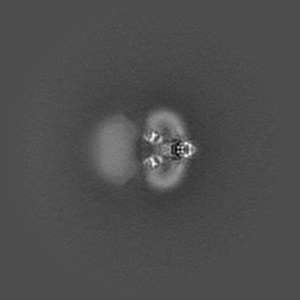

Cryo-EM structure of human Anion Exchanger 1 bound to Dipyridamole

Single-particle3.13 Å

Sample: Dimeric anion exchanger 1 (SLC4A1)